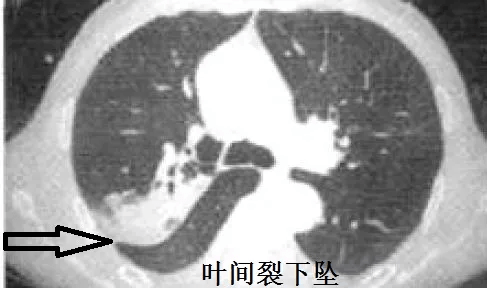

图9

肺炎克雷伯杆菌 , 是肺炎常见细菌 , 典型的影像学表现是 叶间裂下坠 。 什么是叶间裂下坠?书上只有文字 , 我也可以意会到 , 然而画面很模糊 。 多年以后 , 我才突然秒懂!

叶间裂下坠 , 从CT上看 , 就感染的肺组织膨胀了!

肺炎克雷伯杆菌 , 就是这么骄傲的细菌 , 非常喜欢自我膨胀!控制不住的自我膨胀!